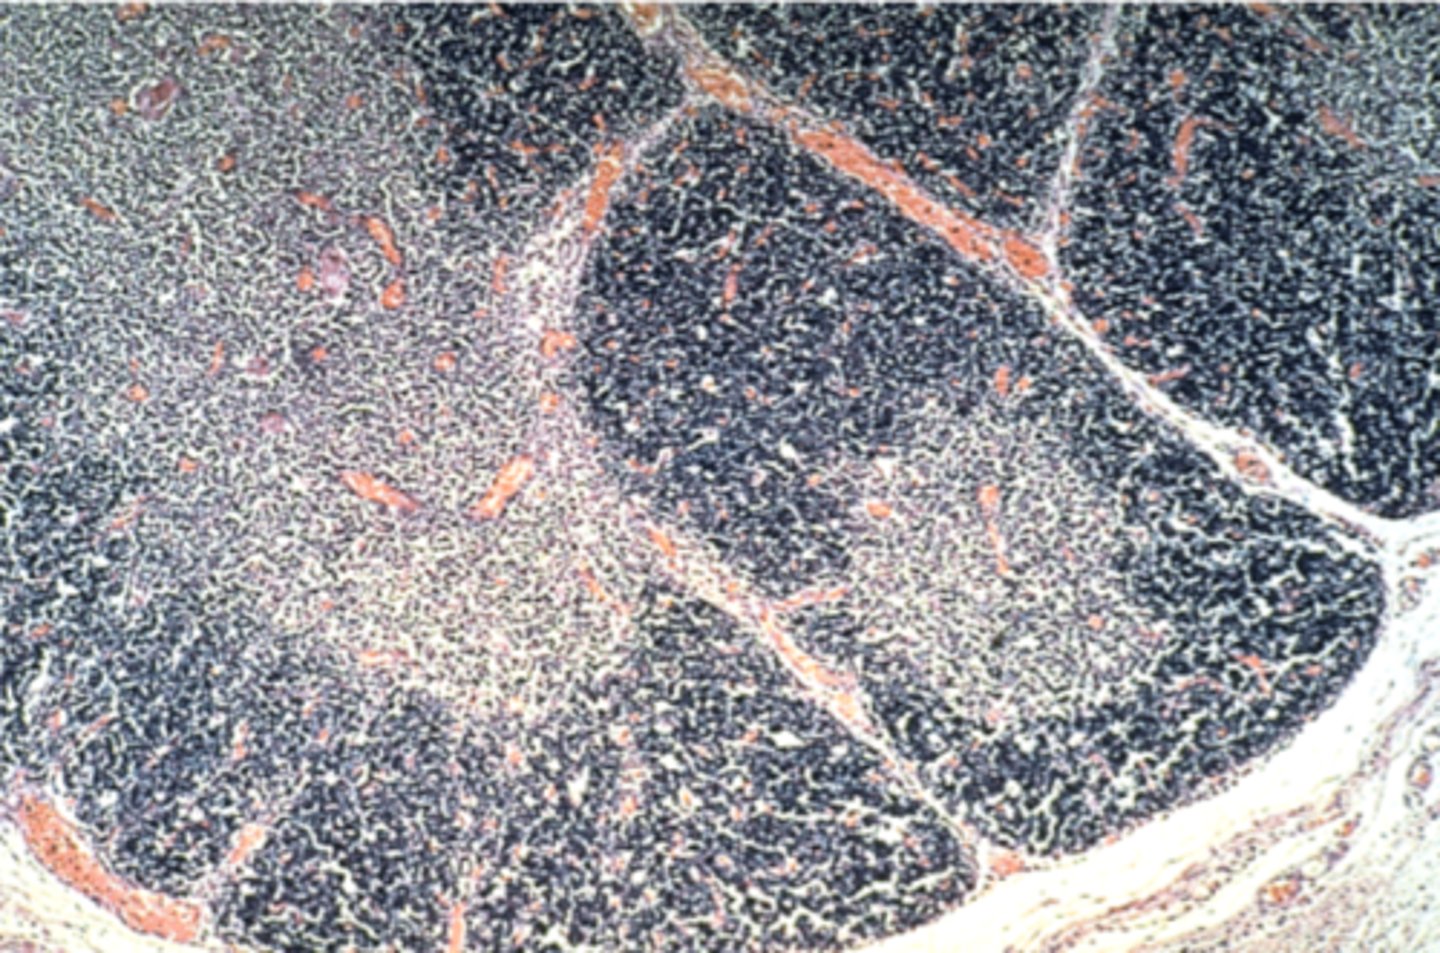

Spleen

What is this?

White pulp in spleen

What is it pointing at?

Thymus

What is this?